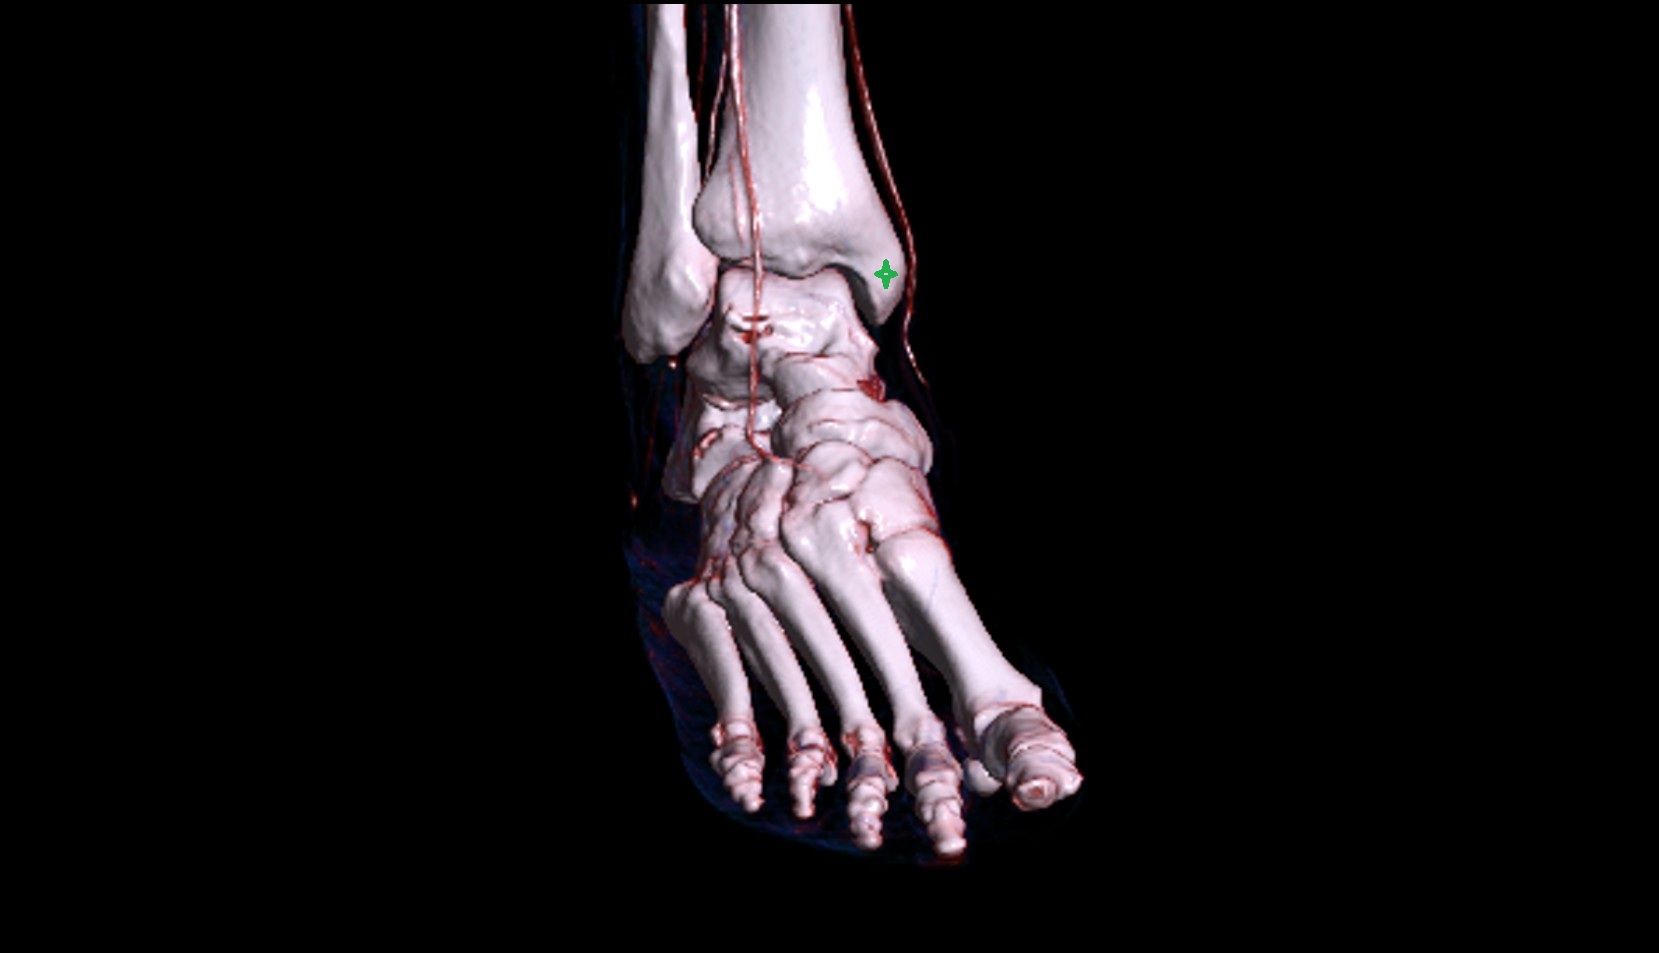

- Talus

- Head of talus

- Body of talus

- Neck of talus

- Calcaneus

- Anterior process of calcaneus

- Sustentaculum tali

- Cuboid

- Tuberosity of navicular bone

- Lateral cuneiform bone

- Medial cuneiform bone

- Intermediate cuneiform bone

- Ankle joint

- Talocalcaneal joint

- Talocalcaneonavicular joint

- Calcaneocuboid joint

- Navicular bone

- First metatarsal bone

- Second metatarsal bone

- Third metatarsal bone

- Fourth metatarsal bone

- Fifth metatarsal bone